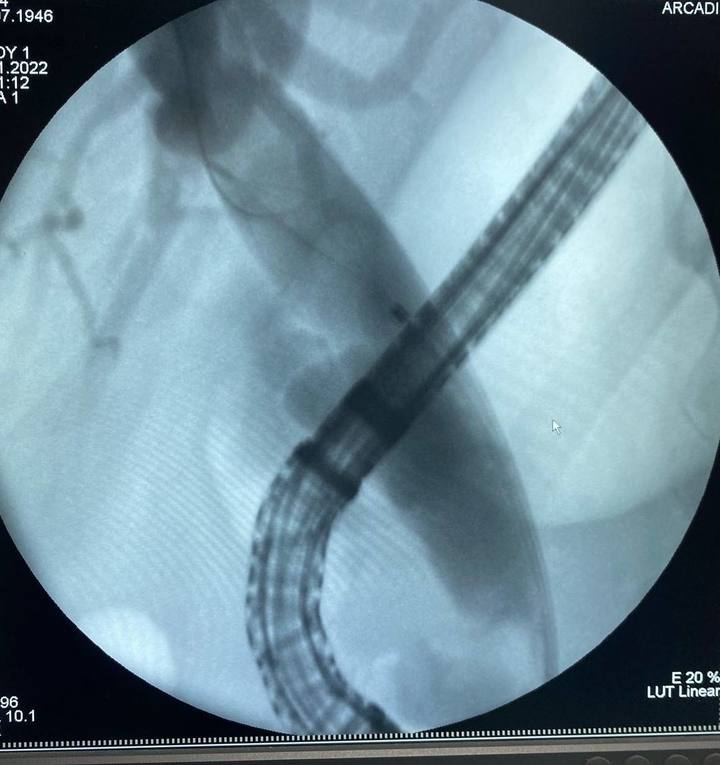

Уникальная операция в Бурятии: события и детали